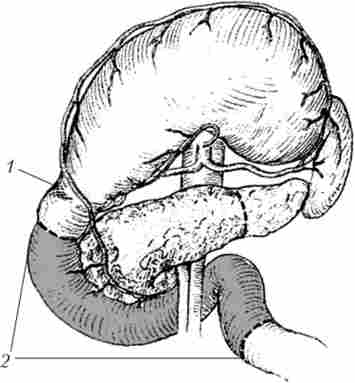

Сполучення жовчного міхура з тонкою кишкою (операція Монастирського) виконується при прохідному протоки міхура. Операція технічно нескладна і малотравматичні, але істотний її недолік - небезпека розвитку рецидиву жовтяниці при проростанні пухлиною протоки (рис. 21.14).

Холецістоеюноанастомоз з міжкишкових анастомозу але Брауну

Мал. 21.14. Холецістоеюноанастомоз з міжкишкових анастомозу але Брауну: